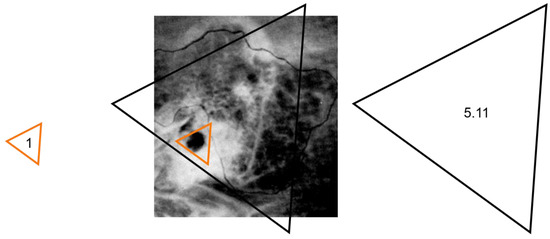

| a | 0–5 | 95 | 5 | 5.97 × 10−1 | 10.72% | 5.11 |

| b | 6–10 | 84 | 16 | 7.54 × 10−3 | 27.56% | 3.14 |

| c | 11–13 | 76 | 24 | 1.33 × 10−1 | 39.80% | 1.71 |

| d | 14–25 | 61 | 39 | 2.62 × 10−1 | 108.51% | 1 |